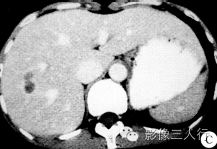

3.肝炎性假瘤多数病灶形态多样,平扫呈低密度,可有纤维分隔,动脉期无显著强化,门脉期和延迟期为轻中度环状强化,间隔也有延迟强化,中心密度较低可不强化,环形强化的内缘可见棘状突起凸向内腔,延迟期病灶境界较平扫清晰,并有缩小感。少数肝炎性假瘤也可呈中心结节状或整体不均匀强化。本例CT征象较符合肝炎性假瘤的常见表现。 医学百科网 | YxBaike.Com

影像诊断:肝右叶占位,考虑①炎性假瘤;②不典型慢性肝脓肿或不典型胆管细胞癌待排除。 医学百科网 | YxBaike.Com

病理诊断:镜下见病灶以纤维组织、小血管、小胆管增生为主,并可见大量浆细胞、嗜酸性粒细胞浸润等。诊断为肝炎性假瘤。 医学百科网 | YxBaike.Com

由于IPL内不同组织形态及动态变化,其影像学表现多样化。IPL的影像特点有:①病灶形态的多形性,CT平扫多为边界不清的低密度区,密度不均匀,一个病灶往往有多个结节融合,形成如类圆形、长条形、花瓣形、串珠形等。②强化方式,由于无动脉血供,增强扫描动脉期一般无强化。门静脉期病灶 表现多样化,病灶可表现为轻或中度宽窄不一的环形强化、分隔状强化、灶周内缘棘状突起样强化、病灶中心核心样强化等,病理与影像学对照,慢性炎性细胞成分不强化,而纤维化成分是造成上述特殊强化形态的原因。延迟扫描病灶强化一般呈从外向内弥散趋势,病灶有缩小感,但瘤灶内部仍达不到等密度。当瘤体内凝固性坏死较少而细胞特别多,或含有较多弥漫分布肉芽组织时,则增强动脉期亦可强化,延迟期呈整体均匀或不均匀强化。③IPL在MRI上呈T1WI等或略低信号、T2WI上随细胞和凝固性坏死的组成比例不同而呈等信号或等高信号。④IPL某些影像征象仅与炎症过程中的特定时期相对应,随着炎症过程动态变化,瘤体的大小、形态及强化类型短期内均可有变化。